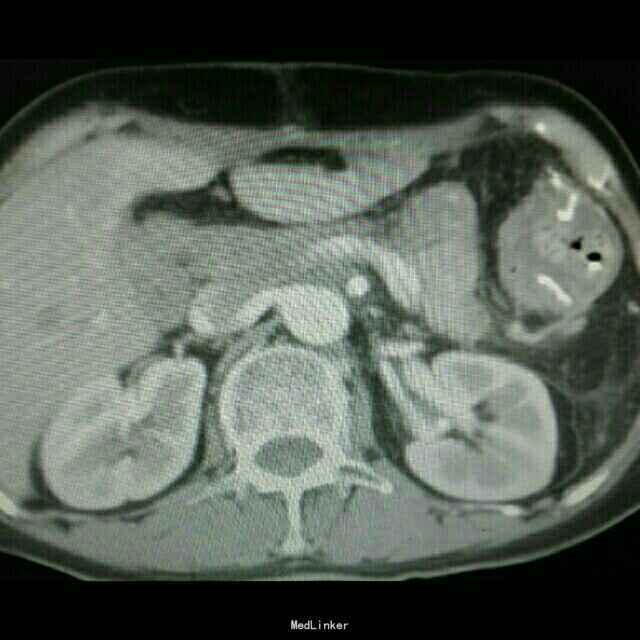

查体:入院后查体腹部平软,未见胃肠型,上腹部正中部可见20cm陈旧性瘢痕,腹部无压痛及跳痛,无肌卫;叩诊鼓音,肝脏及脾脏肋下未及;肝肾区无叩击痛,移动性浊音阴性,肠鸣音弱,1-2次/分。 检查:本次入院后查:WBC:9.2*10^9/L,Na:132mmol/L,余指标基本正常。电子胃镜:胃大部切除术后改变(毕II)吻合口粘膜充血水肿明显,直径约1.2cm,分别尝试进入输入袢及输出袢,见肠腔无明显狭;上腹部增强CT:1胰十二指肠切除术后;2肝脏多发小囊肿;3腹腔内未见明显感染及肿瘤转移征象。上消化道造影:残胃形态、扩张可,未见明显潴留液,蠕动较弱,中远部充盈不佳,胃小肠吻合口宽约1.2cm,未见狭窄及碘水渗漏。胃排空较慢。